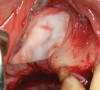

The technique described below is based on a deep buccal full-thickness flap with vertical release in the canine area, followed by creation of a “window” at the lateral wall of the sinus (Figure 2). The bony window is either removed or rotated medially with the sinus membrane and pushed inward. The Schneiderian membrane is then separated from the bone anteriorly, posteriorly, and medially until clinically sufficient space is established (Figure 3). The created space, which occupies the lower third of the sinus, is filled with a bone graft (Figure 4), and the lateral access window is covered with a collagen membrane (Figure 5).

Fig 4. Space is created between the Schneiderian membrane and the sinus walls filled with particulate xenograft.

Figure 4